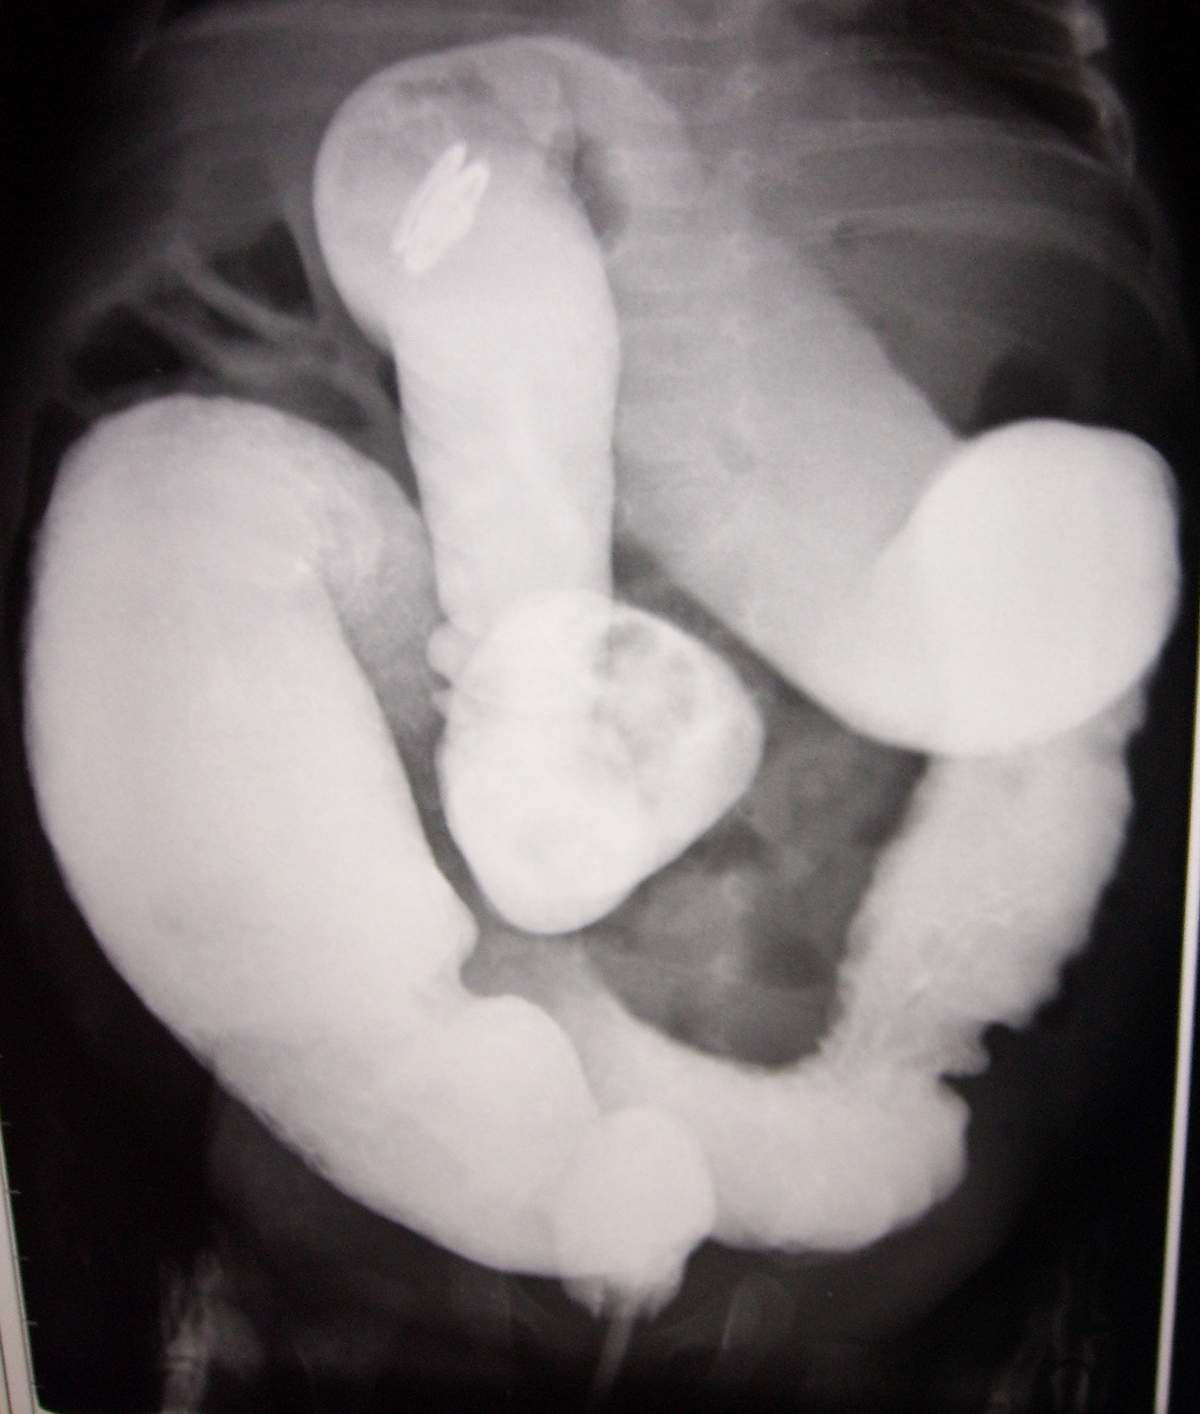

标题: PED0054:[讨论][分享]小儿钡灌肠!

男,2月,腹胀2天。

巨结肠

巨结肠很典型

大家说得都太粗了吧,诊断巨结肠总的说明那一段有问题吧。这样治疗起来才有方向。

我觉得是直肛型的巨结肠,可以先扩扩肛试一下。